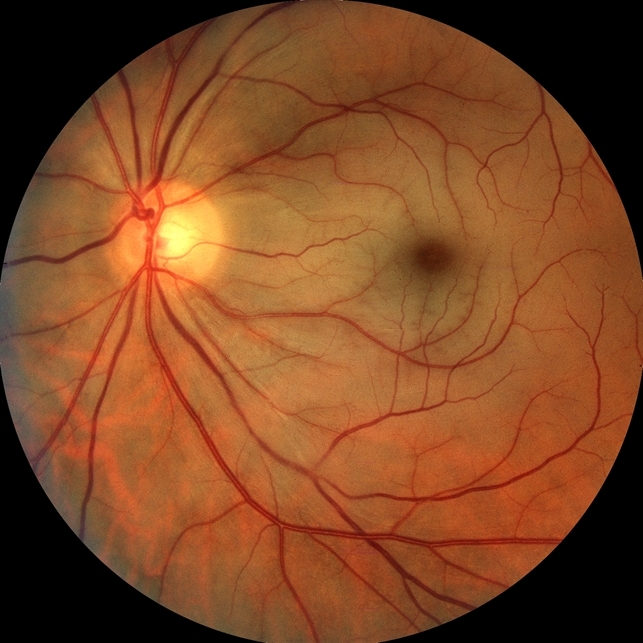

На глазном дне: сетчатка отечна, молочно-белого цвета, контрастирует с вишнево-красным цветом центра макулы. Артерии сужены, неравномерного калибра, кровоток по ним может иметь сегментарный характер. Вокруг истонченной фовеолы — оранжевый рефлекс от интактной хориоидеи в отличие от окружающей бледной сетчатки, что выделяет характерный симптом «вишневой косточки».

В 20% случаев в просвете сосудов определяются желтые холестериновые или белые блестящие кальцифицированные эмболы.

Примерно в 5% случаев встречается функционирующая цилиоретинальная артерия, обеспечивающая кровоснабжение всей или части макулярной зоны. В этом случае снижение зрения может быть не столь значительным и цвет сетчатки не меняется.